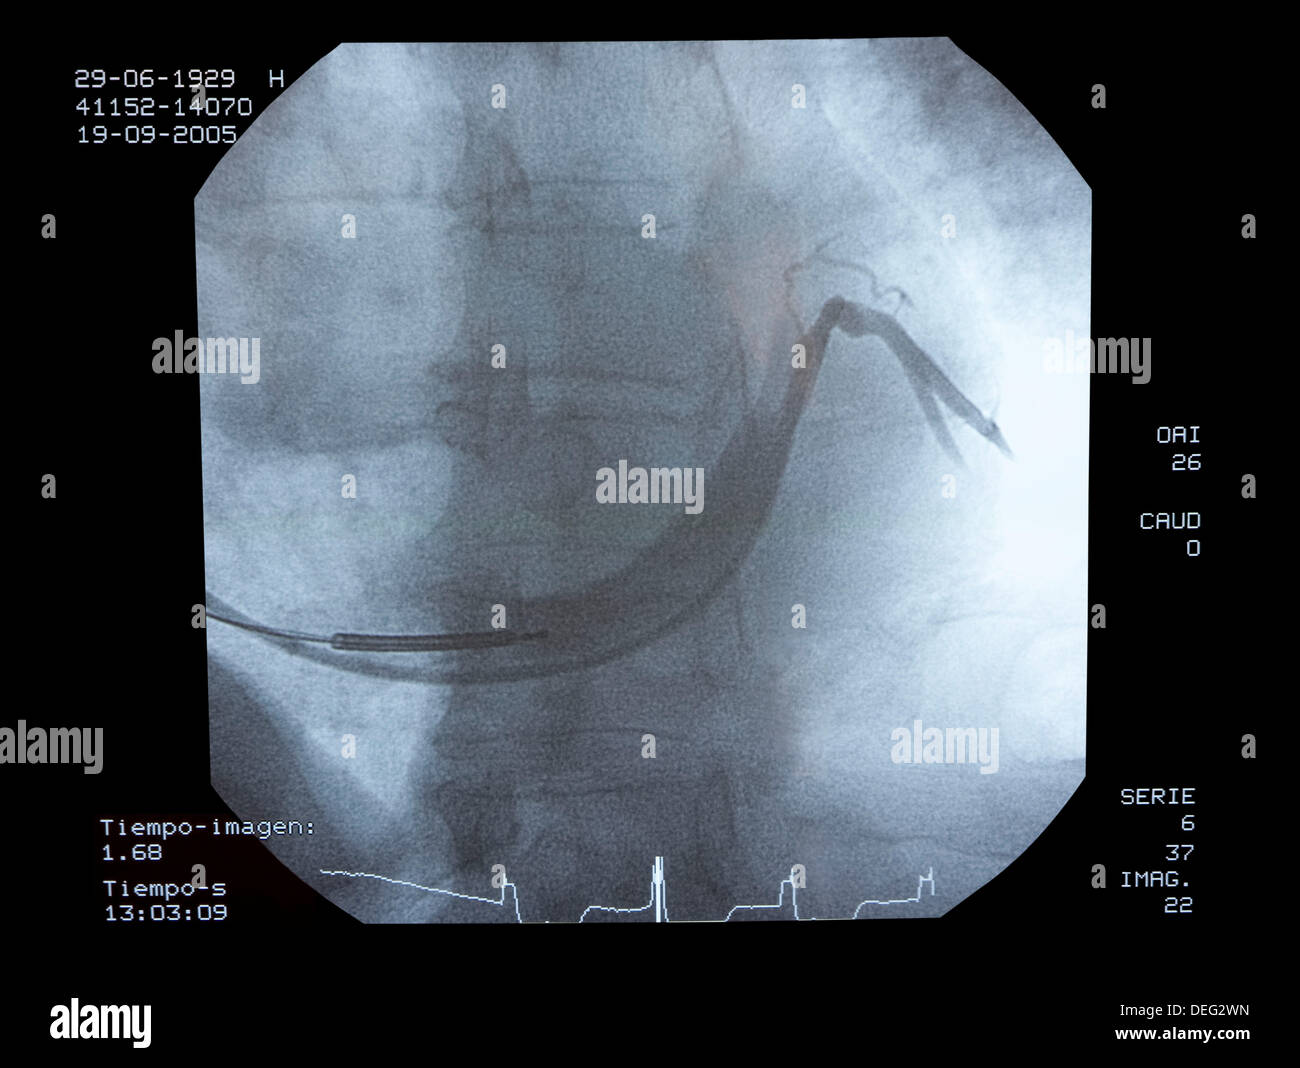

From www.alamy.com

Angiography, implantation of ICD (Automatic Implantable Cardioverter Defibrillator Radiology Automatic implantable cardioverter defibrillators aicds are common cardiac devices designed for both patient monitoring and. In 2009, more than 300,000 adults and children in the united states underwent placement of a new pacemaker or icd, and over 150,000 patients underwent revision [1]. Graphic appearances of cardiac pacemaker and implantable cardioverter defibrillator systems. Cardiac pacemaker and implantable cardioverter defibrillator (icd) systems. Defibrillator Radiology.